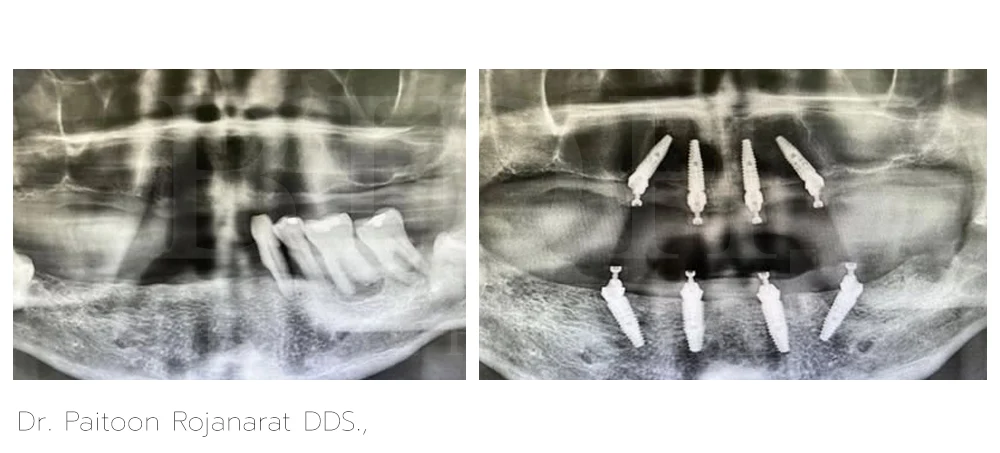

Dr. Paitoon Rojanarat DDS.,

Dr. Paitoon Rojanarat, DDS, is a dentist specializing on prosthodontics and esthetic dentistry that includes crowns, bridges, dental implants, veneers, and teeth whitening. With his highly-skilled and qualified expertise, he crafts custom-made fixed hybrid bridges over implants and dentures over implants designed for a natural appearance and a comfortable fit.